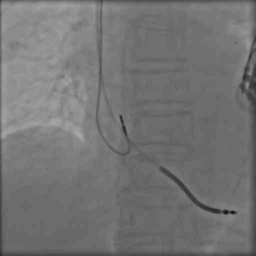

病例五

手术过程

● 冠状窦中段狭窄、成角畸形,经长鞘推送Runthrough导丝至冠状静脉心室侧后静脉远端,沿导丝送左室电极到冠状窦侧后静脉未成功,不除外Vieussen瓣阻挡

使用HI-70RQUE导丝锚定未成功

● 使用6248鞘中鞘辅助加强支撑后顺利沿导丝推送左室电极至靶血管

左室参数:

● 阈值 1.0V 阻抗 580Ω